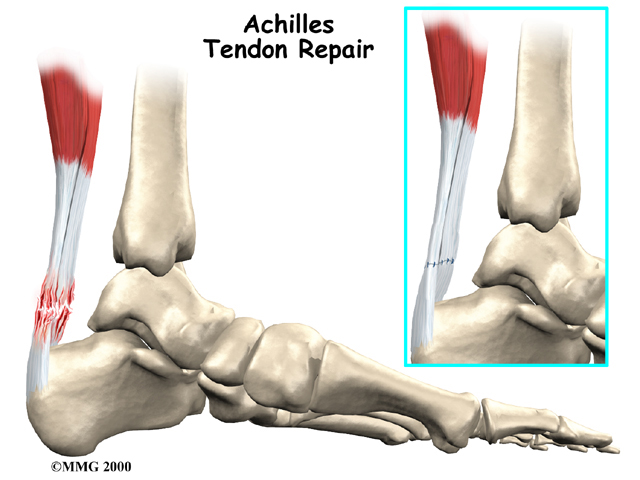

Achilles Tendonitis

Achilles tendonitis is a common issue that develops when the large tendon that extends down the back of the lower leg becomes inflamed. The Achilles tendon connects the calf muscle to the heel bone, and it is the largest tendon in the body. This tendon facilitates standing, walking, running, and climbing.

The robust structure of the Achilles tendon can generally withstand the stress of strenuous movements such as jumping or running, but it is also prone to inflammation due to overuse. Achilles tendonitis also increases the risk of an Achilles rupture, in which the tendon detaches from the heel bone or tears completely in half. Continuing to bear weight upon an inflamed tendon increases susceptibility to a more serious injury (e.g., rupture).

There are two types of Achilles tendonitis: insertional Achilles tendonitis and non-insertional Achilles tendonitis.

Insertional Achilles tendonitis refers to damage of the lower part of the tendon where it inserts (attaches) to the heel bone. This form of tendonitis is common in runners. Non-insertional Achilles tendonitis occurs when collagen fibers in the middle of the tendon begin to develop microscopic tears, usually due to wear and tear. Younger active individuals (athletes) tend to experience this type of tendonitis.